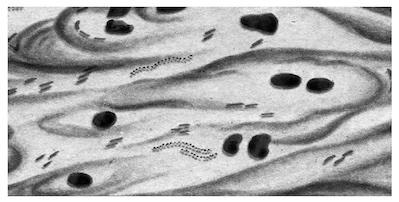

Микроскопическая картина: микобактерии окрашиваются в ярко-красный цвет, остальная микрофлора — в синий или в зеленый (рис. 2.1.1).

Рис. 2.1.1. Микобактерии туберкулеза. Окраска по Цилю — Нильсену

Микроскопическая картина: микобактерии фиолетового цвета, остальные микроорганизмы — красного цвета.